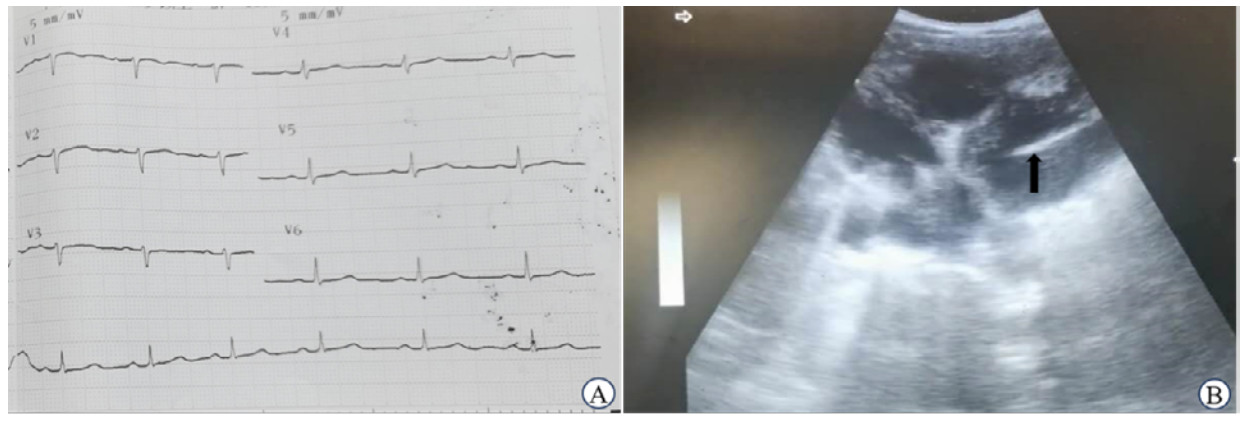

1.2 辅助检查患者实验室检查:白细胞计数7.4×109/L,空腹血糖5.9 mmol/L、血红蛋白95 g/L、血小板计数60×109/L、天门冬氨酸氨基转移酶73 U/L、丙氨酸氨基转移酶110 U/L、人体免疫缺陷病毒抗体阳性、梅毒快速血浆反应素试验阳性、乙肝表面抗原阳性,血吸虫抗体及疟疾抗原检测阴性,医院无法开展凝血功能检查。心电图未见明显心肌缺血性改变(图 1A);肝脏超声检查提示肝实质回声增强,可见弥漫分布的高回声结节,肝左叶可见一圆形无回声区,边界清除,提示肝硬化改变及肝囊肿;使用腹部超声探头于剑突下四腔心切面探查可见左心室内条状高回声,位置和形状固定,周围未探及大的血栓或赘生物影(图 1B)。

| 注:A为患者胸导联心电图检查未见明显缺血性改变(机器肢体导联损坏,纸速:25 mm/s,灵敏度:5 mm/mV);B为使用腹部探头剑突下四腔心切面探查可见左心室内条状高回声影(黑色箭头所示),位置和形状固定 图 1 患者辅助检查资料 |